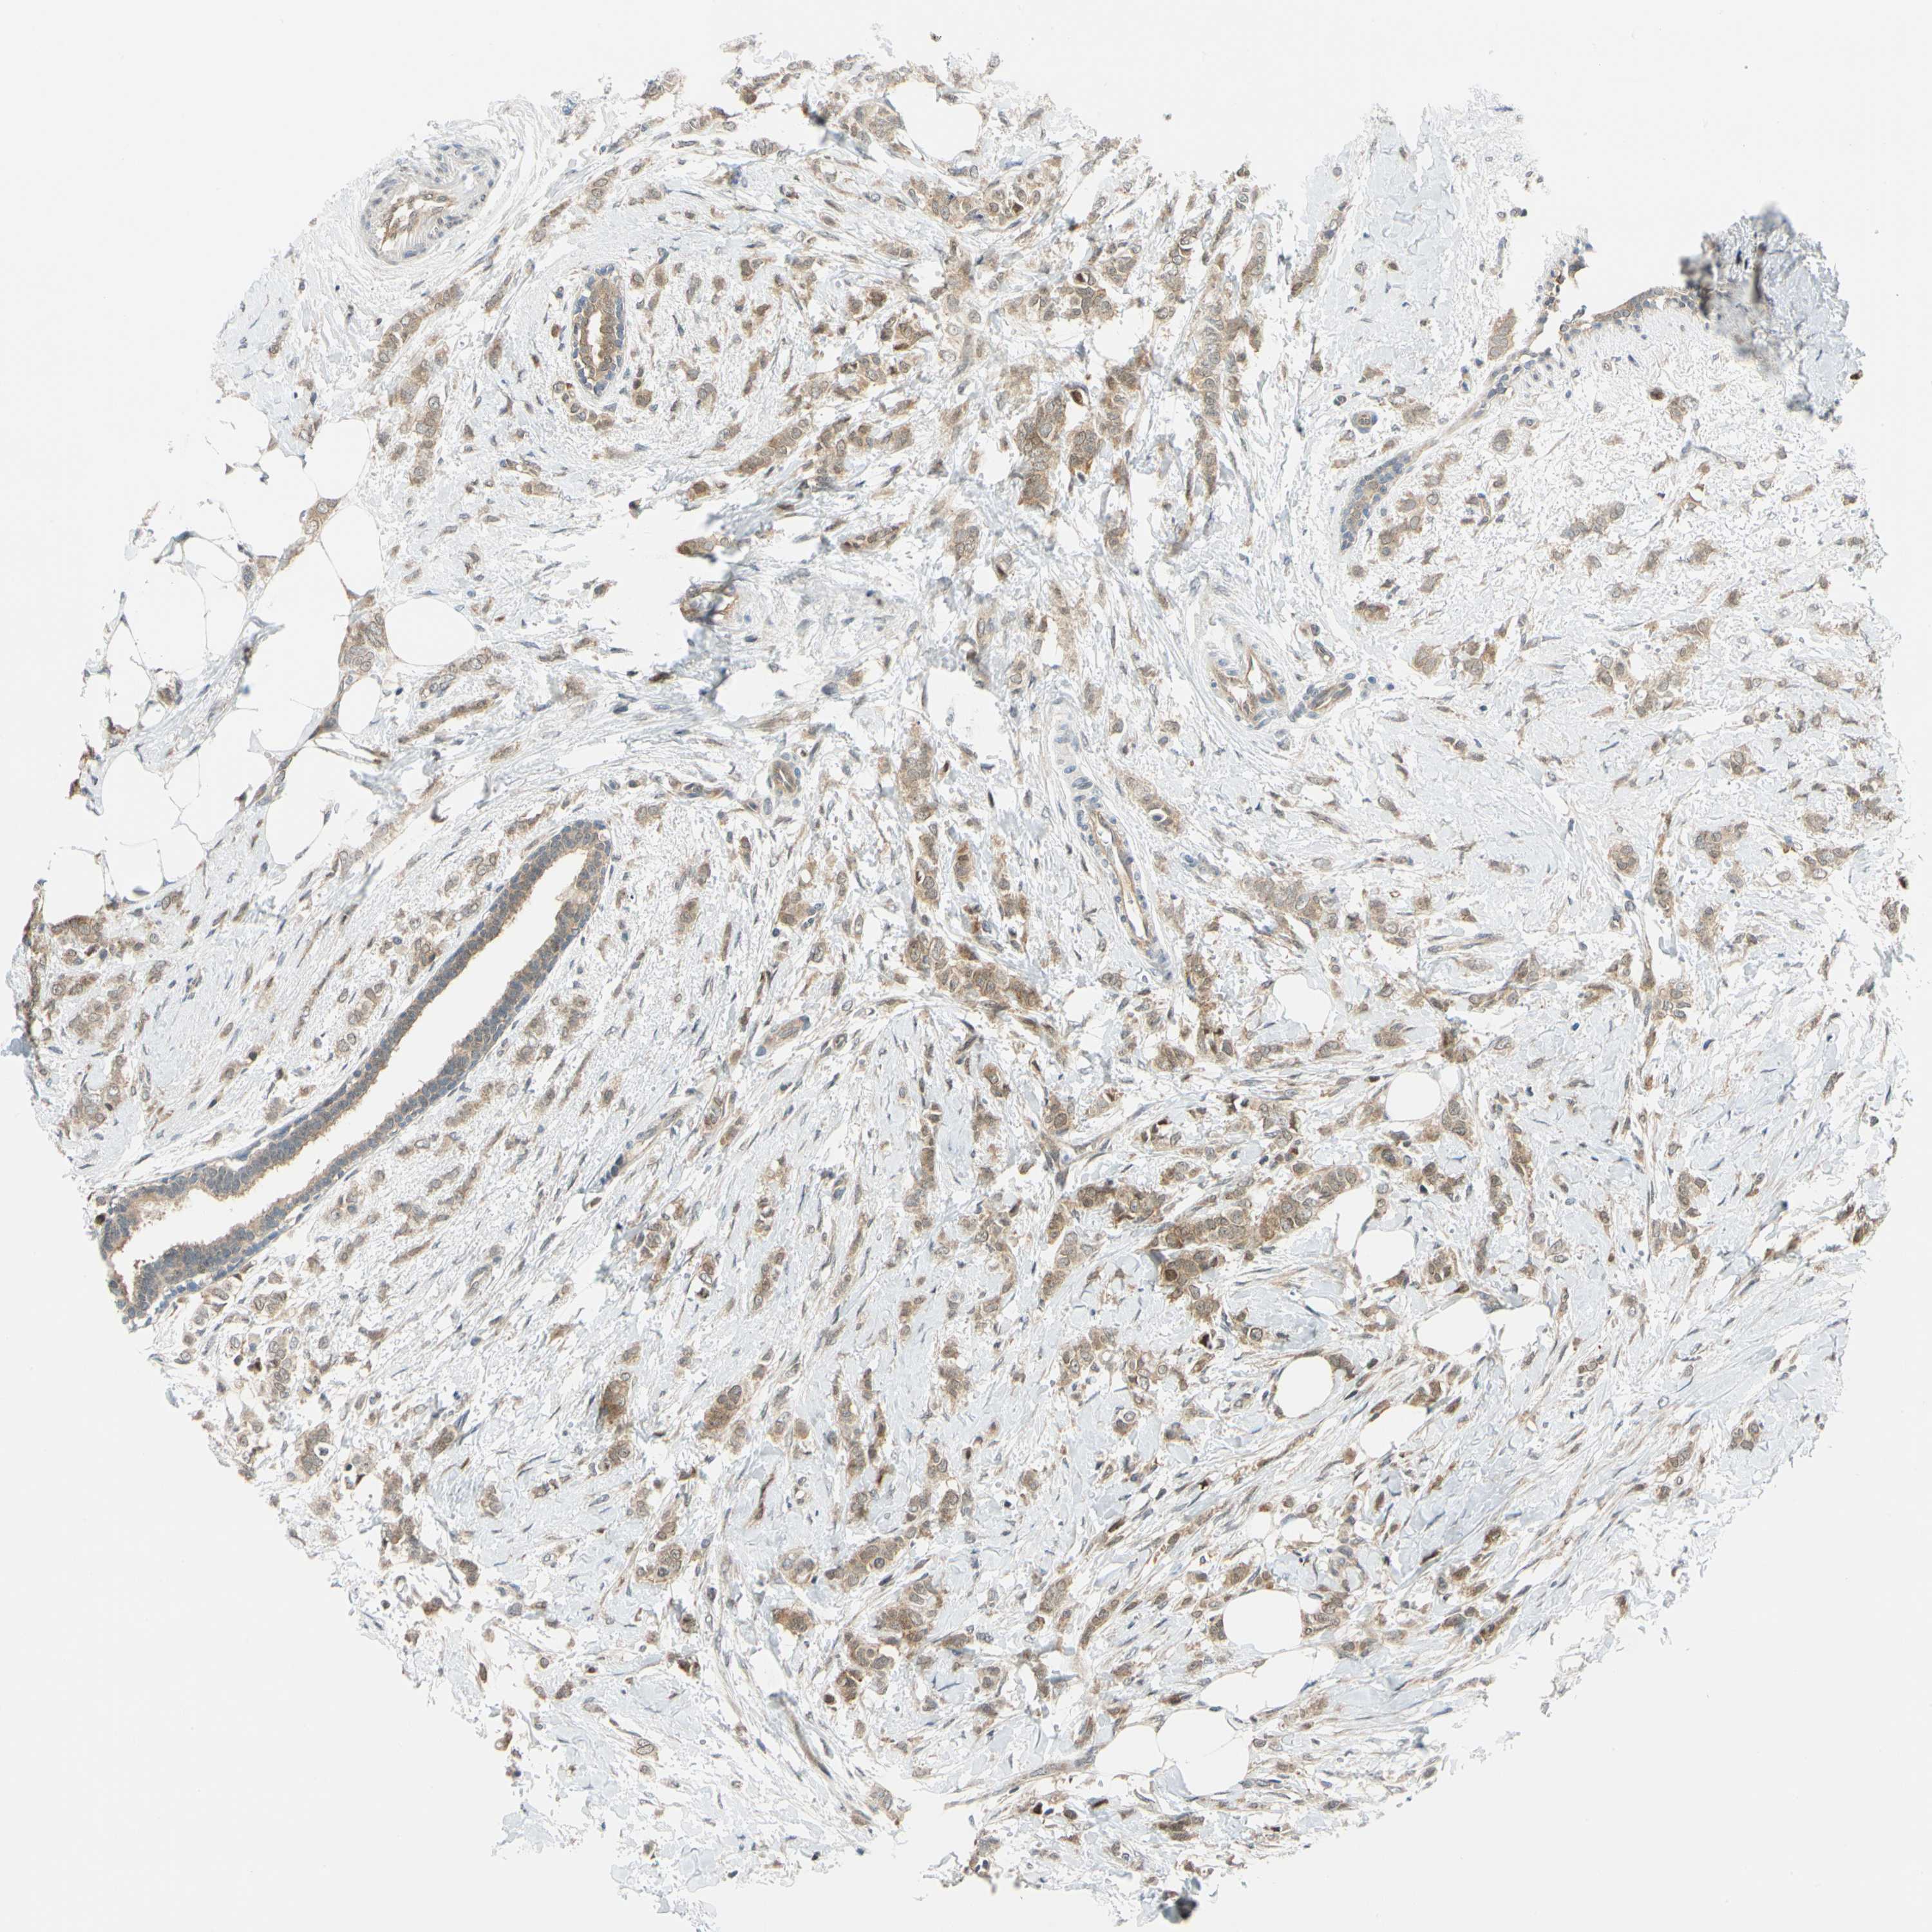

BRCA TCGA BRCA VALIDATION PROTEIN EXPRESSION